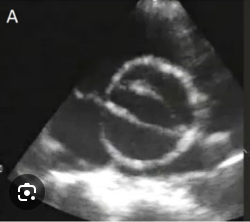

Two-Dimensional evaluation of AoV

WHAT SETTINGS

WHAT VIEWS

• Obtain careful, high resolution imaging focusing on the aortic valve in both harmonics and fundamental modes in the parasternal long axis view and short axis view

o Use magnification (zoom)

bicuspid aortic valve- most common way it happens

football

this type of bicuspid aortic valve is less common

football